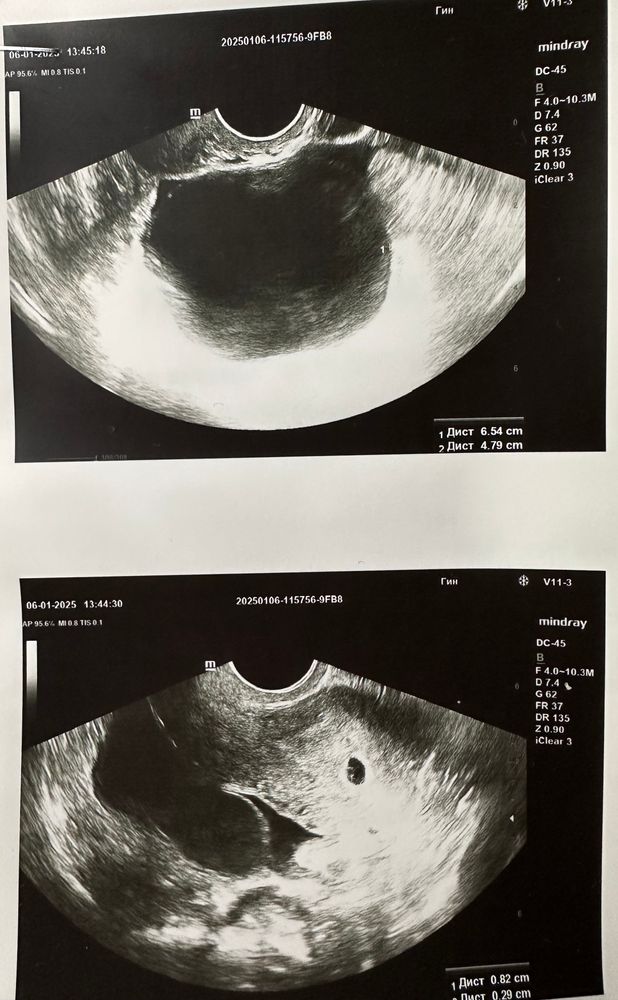

Беременность маточная по сроку 5,1. Плодное яйцо 8,2мм, желточный мешок 2,9мм.

Так же, обнаружена огромная функциональная киста в 64мм, а желтого тела из-за неё не видно😭😭😭